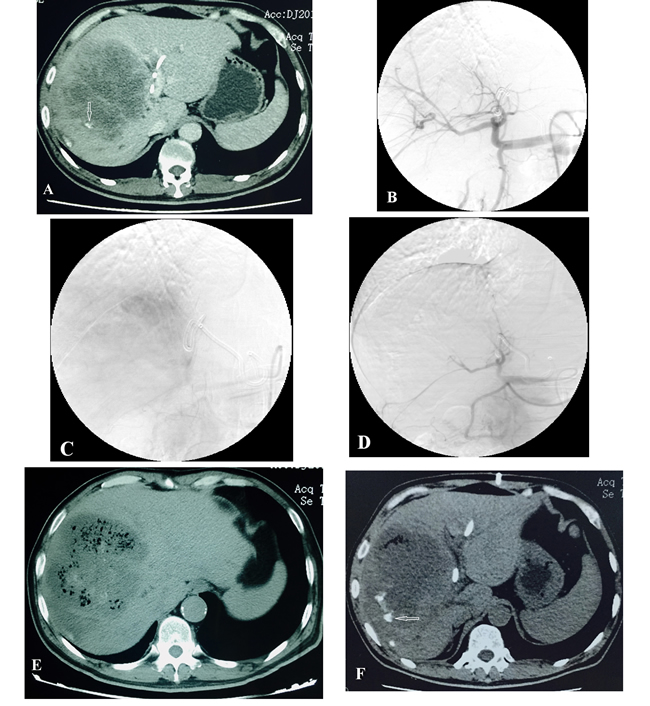

All patients were selected from among the patients attending the Interventional Therapy Department of our hospital between August 1, 2015, and February 29, 2016. Patients were eligible for inclusion if they had 1) a confirmed non-hypervascular malignant tumor of liver, and were unwilling or unsuitable for surgery; 2) TMGs only was applied during the embolization, no other embolic agents such as iodized oil, gelatin sponge and so on. Patients with poor Life expectancy (<3 months) were excluded, such as liver tumor rupture and bleeding. Definition of non-hypervascular malignant tumor of liver: Two senior imaging physicians unanimously determined that intrahepatic tumors showed no enhancement or mild enhancement in the arterial phase of CT enhancement (The average CT value of arterial phase increased less than 20 Hu than plain scan in the lesion) [Figure 1A].

We followed a standard treatment procedure. First, angiography of the common hepatic artery was performed to identify the feeding arteries [Figure 1B, 1C], including unusual feeding vessels such as the inferior phrenic artery, superior mesenteric artery, and so on. We used a microcatheter to superselectively target the feeding artery and then slowly injected the microspheres for embolization. In view of the relatively sparse blood supply and the small blood vessels in non-hypervascular tumors, only 2 sizes of microspheres (Embosphere; Merit Medical Systems Inc., South Jordan, UT, USA) were used in this study, namely, 100-300 μm and 300-500 μm. After the microcatheter reached the target blood vessel, the microspheres suspension was prepared [11]: 1 mL microspheres was added into a 15 mL mixture of physiological saline solution and iodinated contrast agent (in a ratio of 1:1). This was drawn into a 20 mL syringe (which functioned as a storage syringe). A 1 mL syringe (which functioned as the injection syringe) was then connected to the 20 mL syringe via a three-way stopcock, and the suspension was mixed by repeated suction and expulsion. The microcatheter was then connected, and the microspheres suspension was injected slowly into the target vessel. As a cost-saving measure, the 100-300 μm microspheres were injected first, and microspheres of larger size were used only if the embolization was not sufficient. When fluoroscopy demonstrated slowing of blood flow, angiography was performed to confirm that the tumor vessels had disappeared, after which the procedure was terminated [Figure 1D]. If the tumor vasculature reappeared 5 minutes after the embolization, the procedure was repeated.

The local reactions of all patients after TAE are shown in Table 3. In the 6 patients, 0 case of complete response (CR) and 6 cases of partial response (PR) after TAE were observed, the tumor necrosis rate reached 48%-73%. Three months after TAE, there was no case of CR, 1 case of SD, 2 cases of PR, and 3 cases of PD; the tumor necrosis rate was 22%-68%. In two of the larger lesions (maximum diameter >10 cm), large areas of necrosis associated with bubbles were observed on CT scan 1 week after TAE [Figure 1E, 1F].

Figure 1: Male patient, 54 years old, with hepatocellular cholangiocarcinoma. CT scan shows a hypovascular tumor. The patient had undergone PTCD and TACE (with 1 week interval) 1 month earlier. At review, there was increase in the size of the tumor. Microspheres TAE therapy was applied immediately. A. CT scan shows lesions located in the right lobe of the liver before TAE, poor blood supply, and a small amount of lipiodol deposited around the edge of lesion (white arrow). B. C. Hepatic artery angiography before embolization, shows that the blood supply is not rich. D. After embolization, the tumor blood vessels have disappeared, and the main and secondary branches of the hepatic artery are visible. E. CT plain scan 1 week after embolization shows visible tumor necrosis; many bubbles can be seen. F. Three months after embolization, most lesions have undergone necrosis; a small amount of gas and a little lipiodol deposition can be seen at the edges of the lesions (white arrow).